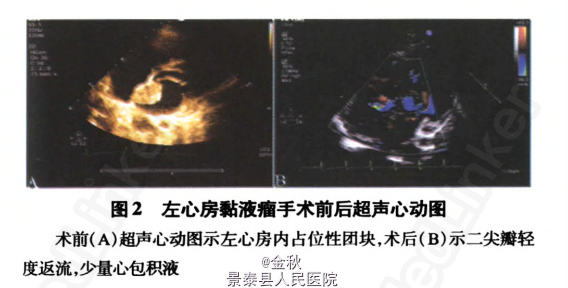

查体——血压120/75mmHg;心律齐,各瓣膜区未闻及病理性杂音。神经系统查体:神志清楚,言语清晰,应答切题,查体合作;双侧眼球运动灵活,双侧瞳孔等大等圆,直径3 mm,对光反射存在;右侧鼻唇沟稍浅,伸舌居中,咽反射存在;颈软;右上肢肌力4级,右下肢肌力5级,左侧上、下肢肌力5级,肌张力正常;生理反射存在,右侧巴宾斯基征阳性。 辅查——血常规:白细胞计数7.6×109/L,中性粒细胞比例62.8%,红细胞计数4.06×10 12/L,血小板计数192×109/L,血红蛋白112 g/L;C一反应蛋白0.2mg/l;红细胞沉降率:50mm/l;总蛋白:89g/l,球蛋白40.1g/L;IgA3.47g/l,IgG 23.1g/l,IgM3.09g/l;D一二聚体0.3mg/l;肝功能、肾功能、血脂、电解质、铜蓝蛋白、同型半胱氨酸、抗心磷脂抗体、自身抗体全套、血抗中性粒细胞胞质抗体、肌酶、凝血功能、甲状腺功能和各种肿瘤标记物水平均在正常范围内。心电图:窦性心动过速,心率102次/min,ST-T段改变。超声心动图:左心房内占位性团块,左心房黏液瘤可能性大(图2A)。

诊断——左心房粘液瘤并多发性脑梗死。 处理——人院后予阿司匹林抗血小板,低分子肝素钙抗凝以及活血等治疗。确诊后,患者在人院第4天转心胸外科行心脏肿瘤切除术,术中见肿瘤位于左心房,大小约30mmX 40mmX 40mm,有一窄蒂连于房间隔,完整摘除左心房肿瘤。术后病理学检查:心脏黏液瘤(图3),肿瘤大小25mmX20mmX12mm。术后第6天复查超声心动图:二尖瓣轻度返流,少量心包积液(图2B)。